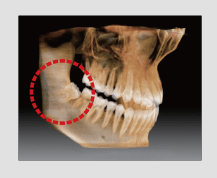

Normalmente, una imagen de 10x8.5 muestra el diente No.8. Sin embargo, cuando los terceros molares están tumbados sobre su lado hay una gran posibilidad de que el diente se corte de la imagen.

El “volumen en forma de arco” elimina esta posibilidad y muestra el área de dentición oculto.